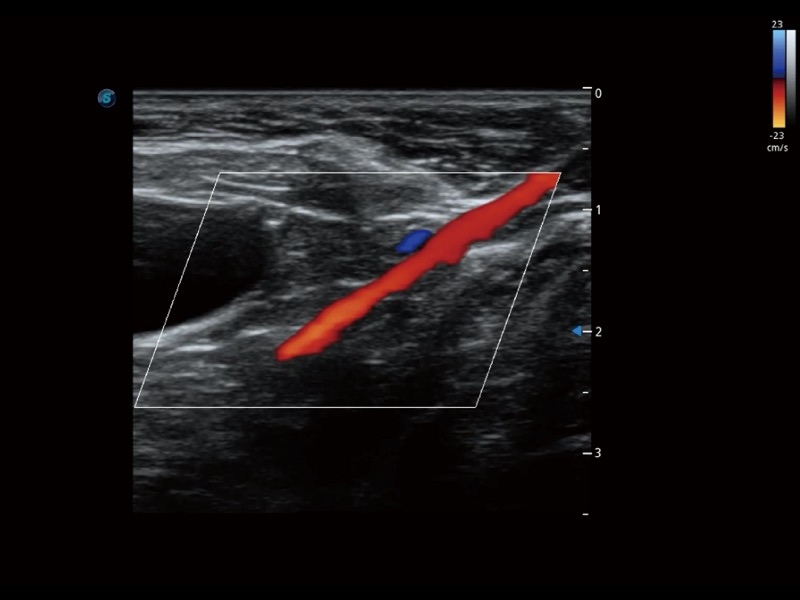

通過創(chuàng)新的 Matrix E自適應(yīng)濾波器和超長時(shí)間域算法,極大提升超低速微細(xì)血流的檢出能力,同時(shí)更精準(zhǔn)地濾除軟組織和噪聲信號,為獸用醫(yī)生提供以往無法通過常規(guī)血流獲得的疾病診斷信息。

通過色彩血流和實(shí)時(shí)寬景相結(jié)合,可觀察到完整的靜脈或動(dòng)脈的血流,方便醫(yī)生檢查。實(shí)時(shí)掃查過程中,如有任何操作失誤也可以很容易地進(jìn)行回掃擦除,而不會中斷掃查。